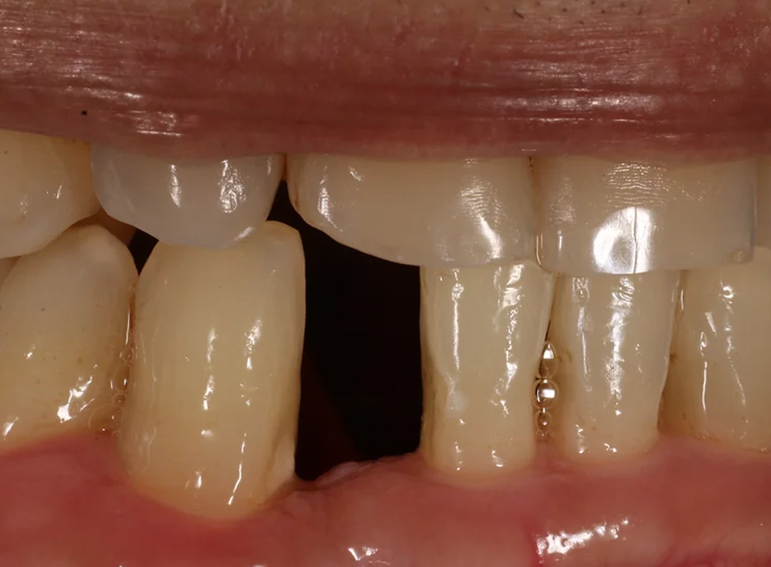

Missing lower incisor replaced with an adhesive bridge.